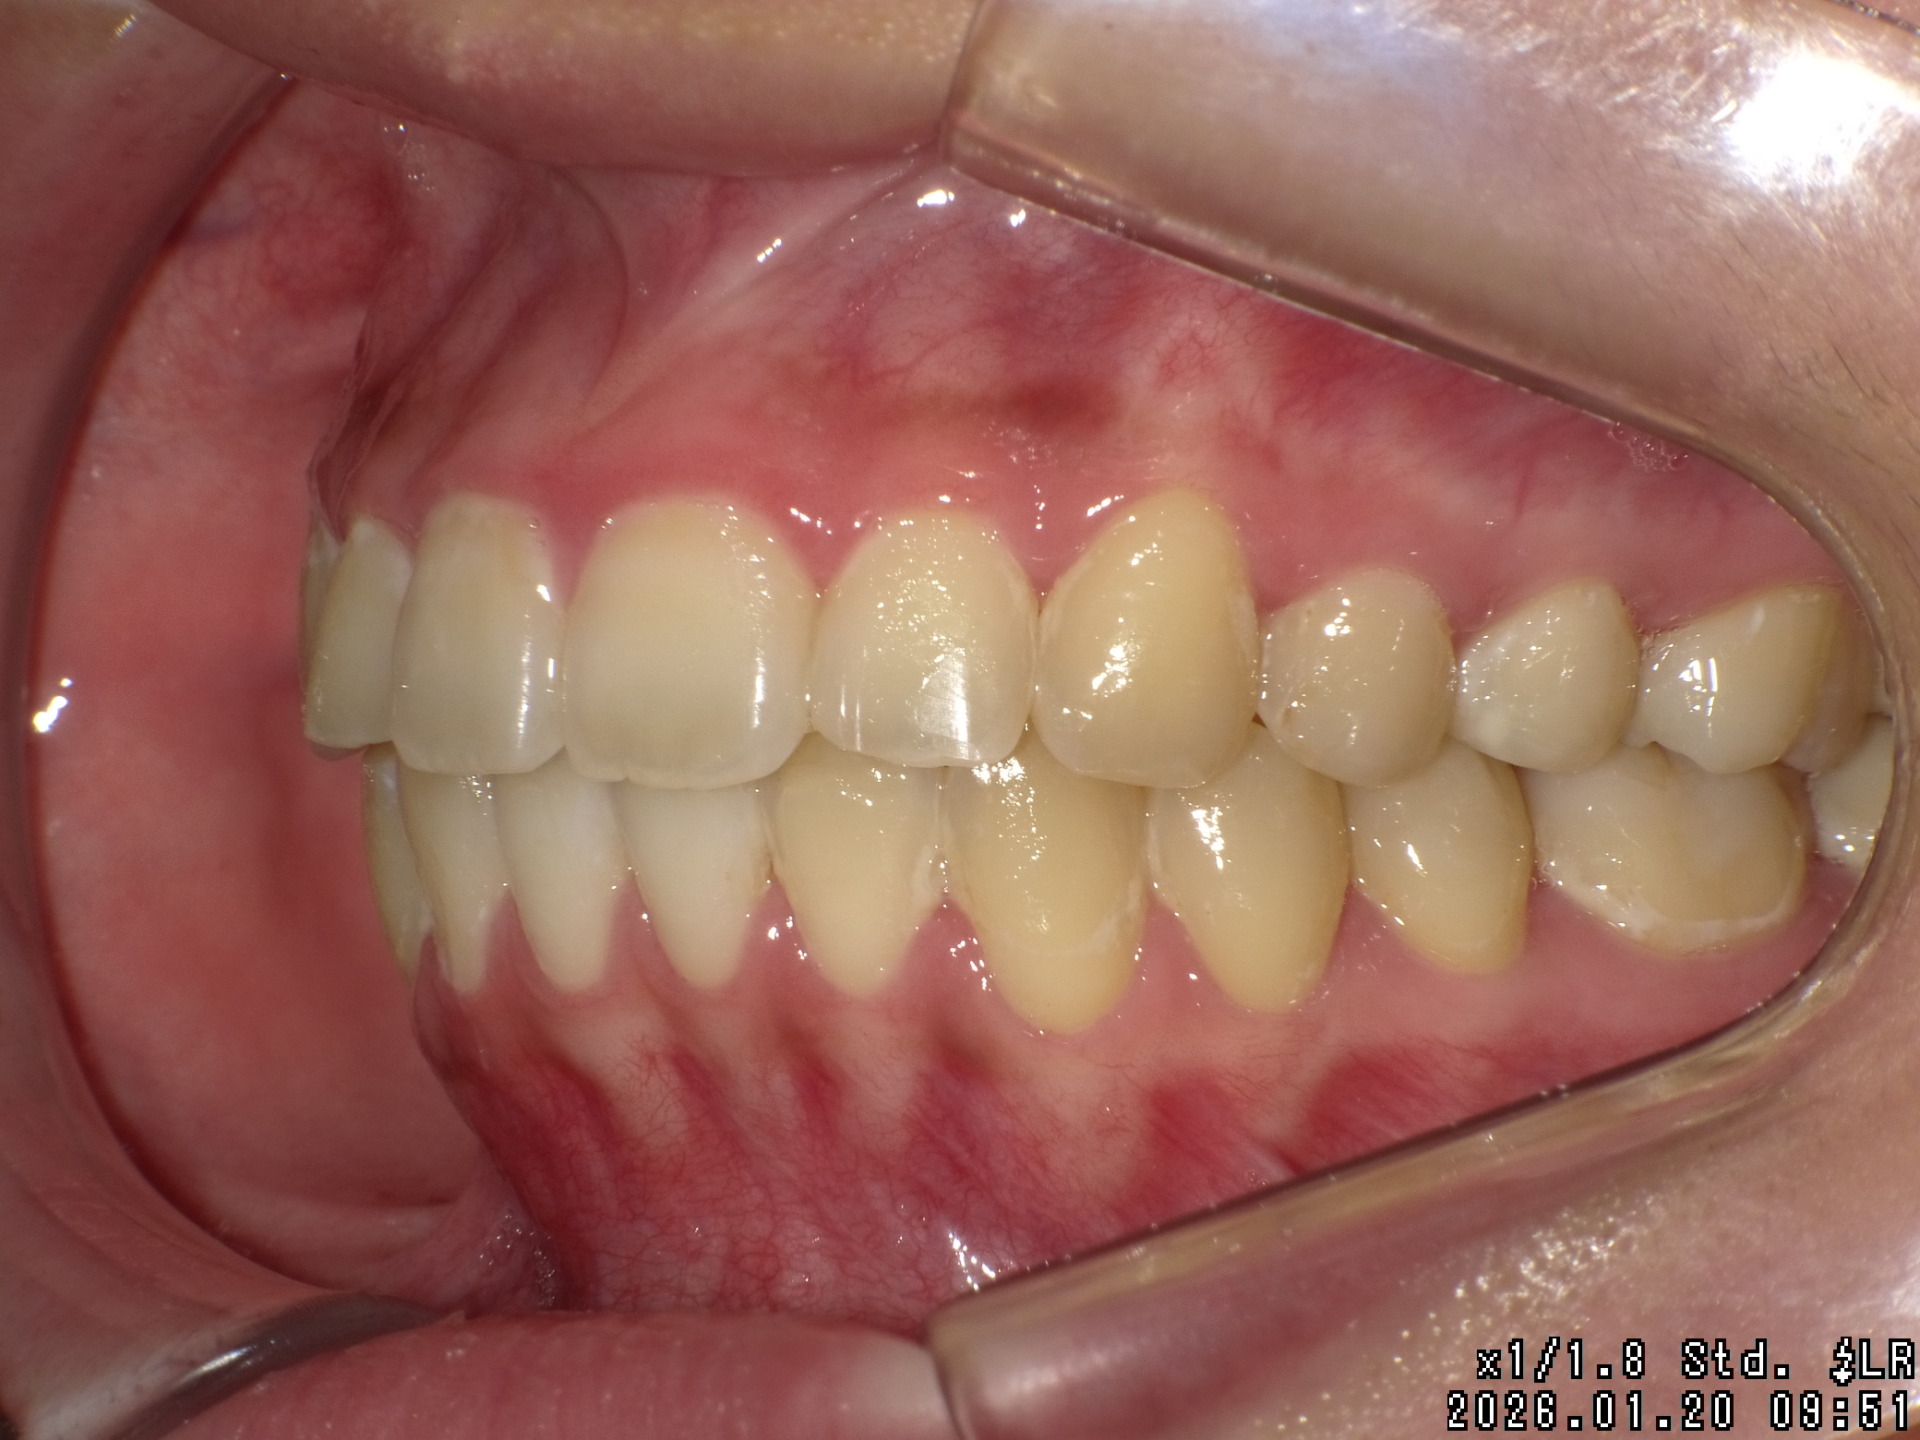

途中経過